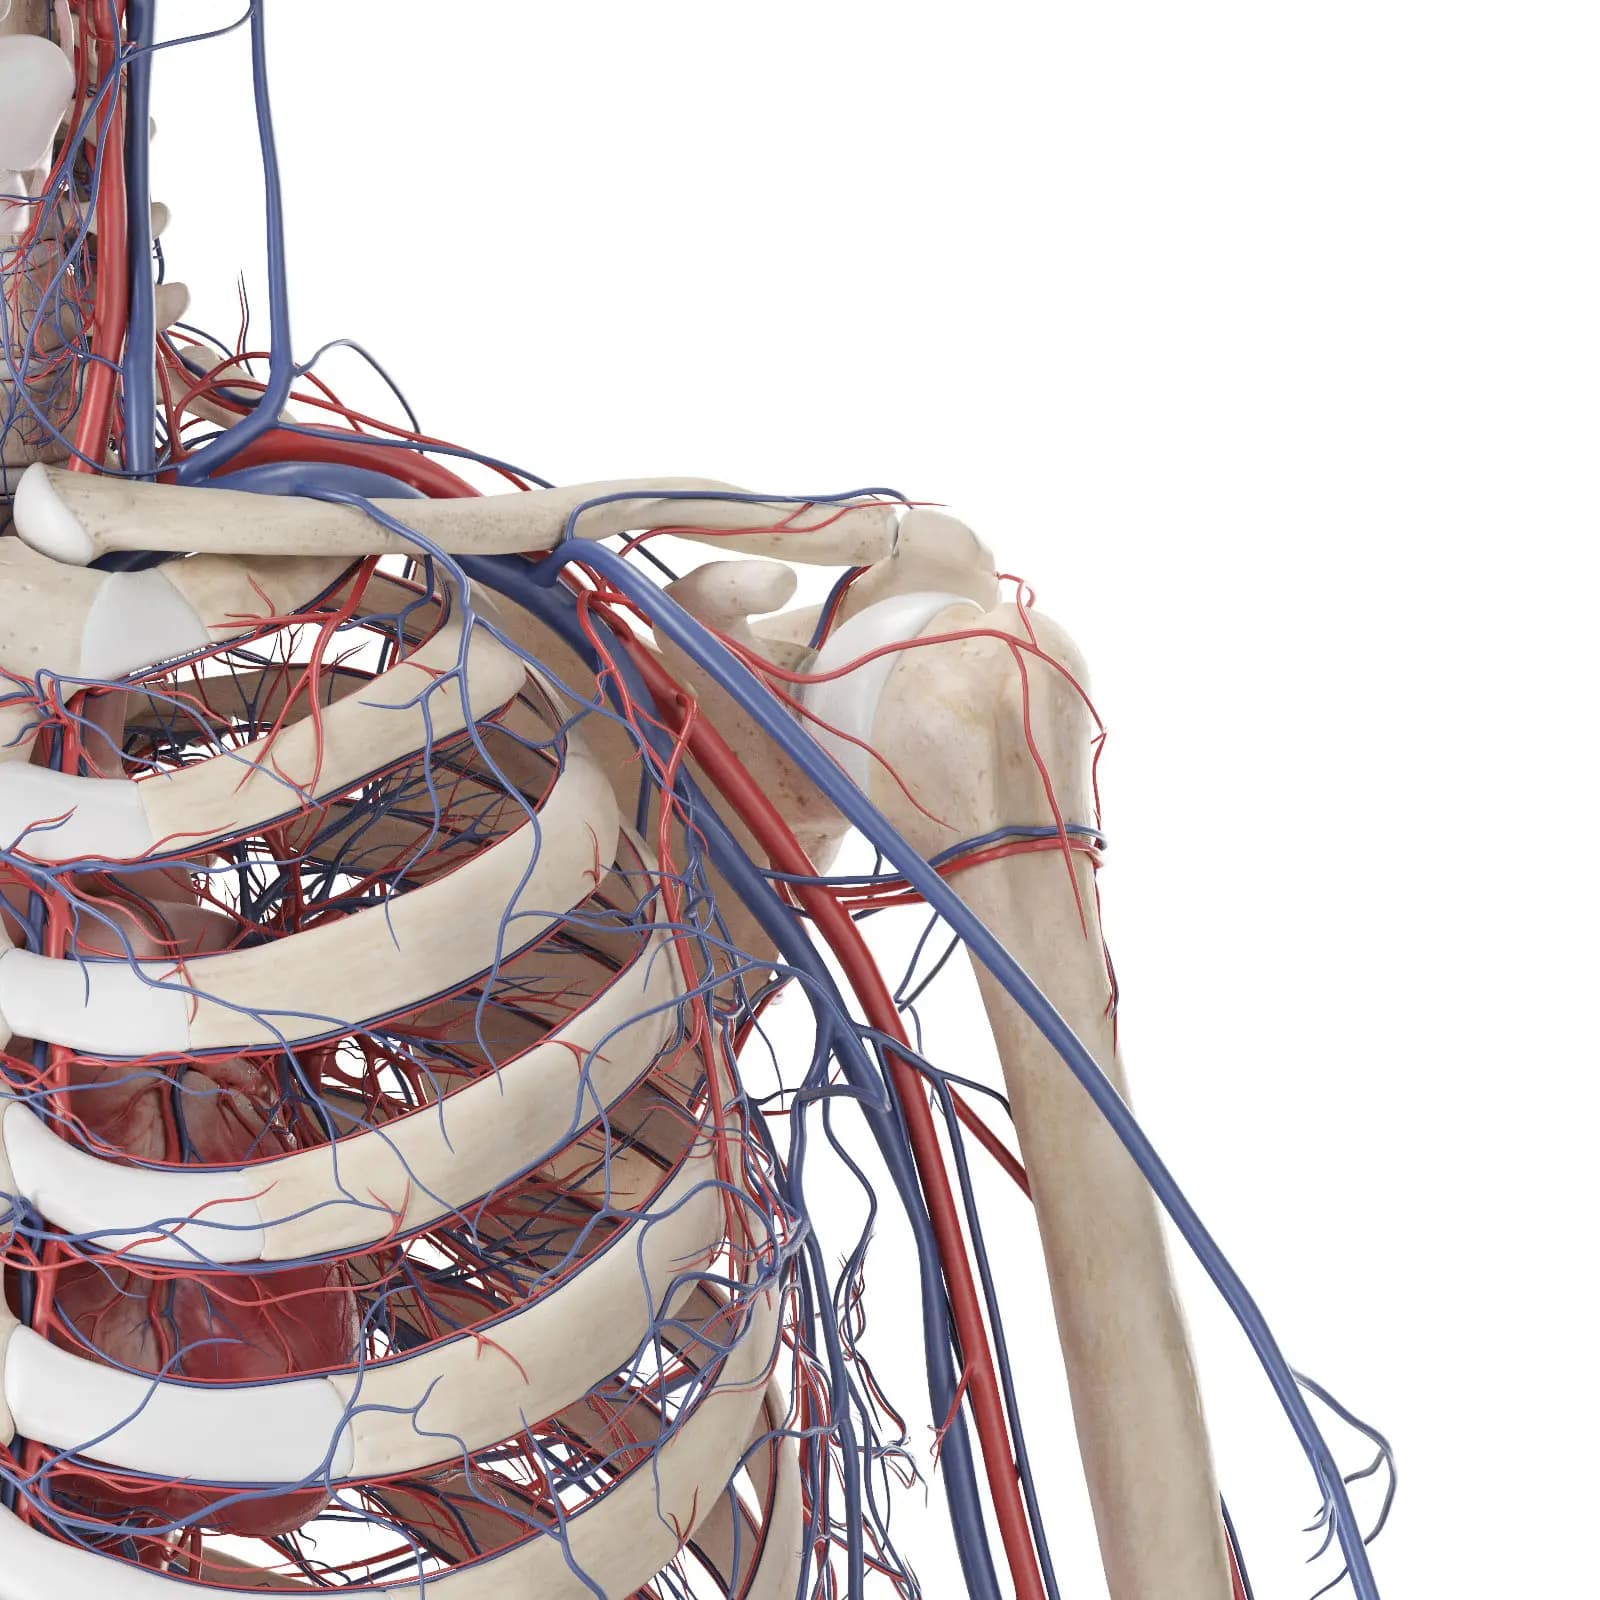

3d Rendered Medical Illustration Of The Vascular System Of The Shoulder And Upper Back

3d Rendered Medical Illustration Of The Vascular System Of The Shoulder